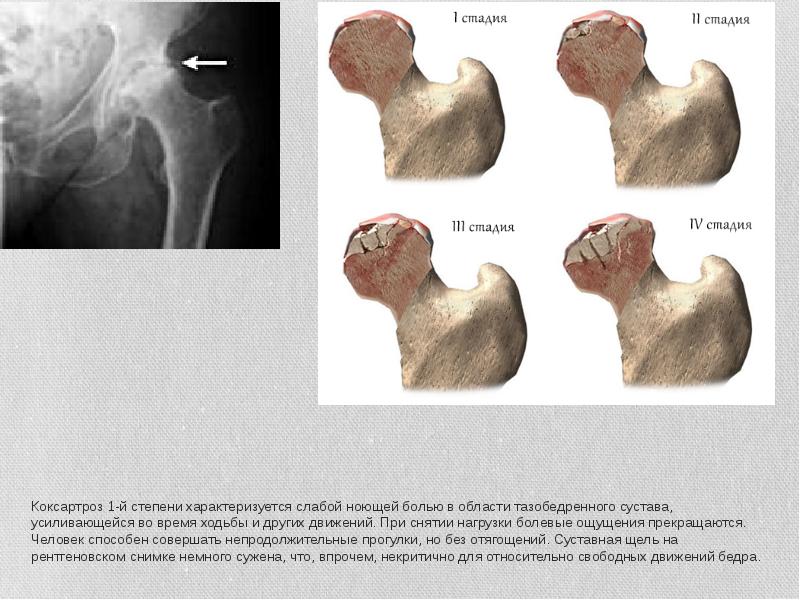

- 5. Коксартроз 1-й степени характеризуется слабой ноющей болью в области тазобедренного сустава,